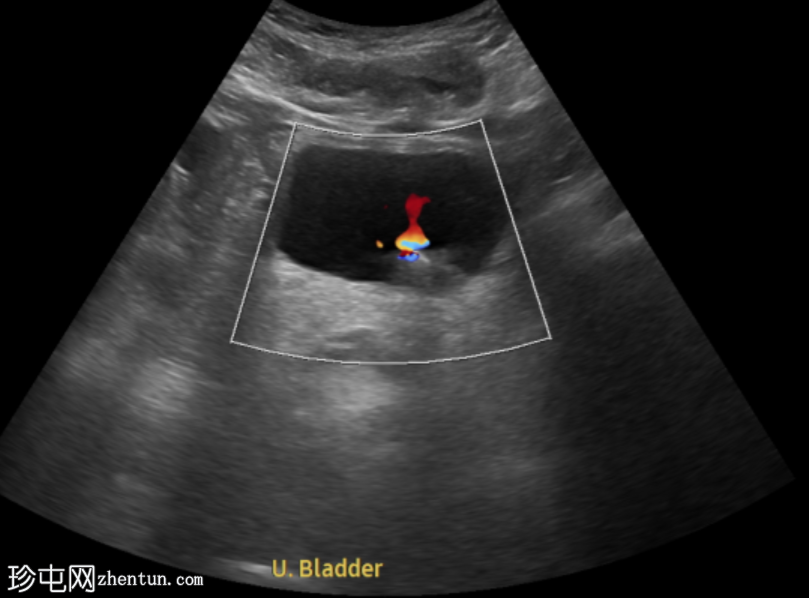

超声显示左侧轻度肾积水,由膀胱输尿管连接处一枚7毫米的远端输尿管结石阻塞所致,输尿管射流正常。

肾积水并非总是由输尿管结石引起。肾盂和肾盏扩张的程度与结石大小并不一定相关。

较小的结石有时可导致中度上游扩张,而较大的结石可能仅引起轻微的充盈感,这取决于患者的引流和水合状态。